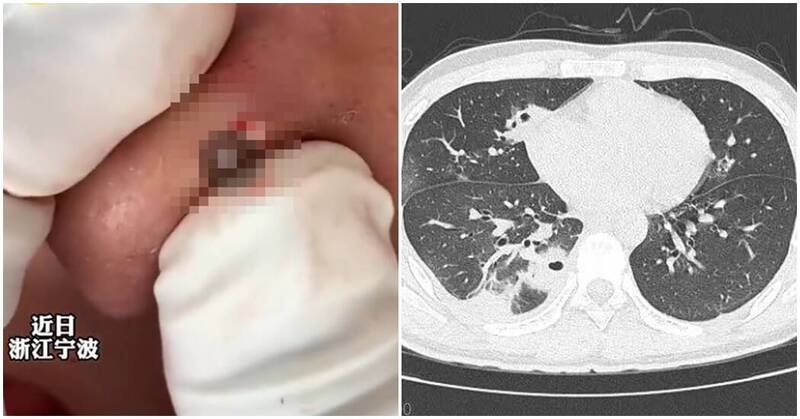

一名58歲陳姓女子因車禍自撞,全身多處重創、生命垂危,送醫後檢查發現其胃部與腸道竟因撞擊力擠入胸腔,胸腹部嚴重受損。外科部主任馮啟彥採用腹腔鏡微創手術,成功修補多處破裂,將傷者從鬼門關前救回。陳姓女子送